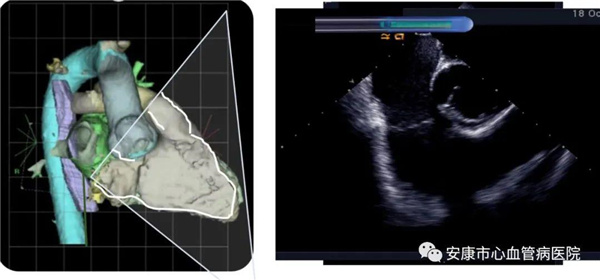

心律失常團隊在11月6日為患者在ICE引導下行房撲射頻消融術。穿刺左鎖骨下靜脈,導絲走行證實了合并永存左上腔靜脈。穿刺右股靜脈,分別送入心腔內超聲導管和消融電極,超聲下建立右心室、右心房、左心室、左心房、二尖瓣和三尖瓣及三尖瓣峽部模型。ICE就像術者多了一雙天眼,可以對心臟內部結構一目了然,360度無死角觀察心臟結構,可以做到“所視即所及”。建模后,消融三尖部峽部,房撲很快終止,轉為竇性心律,手術獲得成功!手術用時僅70分鐘,術后病情穩定,安全返回病房。

心腔內超聲(Intracardiac Echocaiography ICE)是將微型的換能器安裝在心導管的尖端,再經外周血管(動脈或靜脈)送至心腔,換能器發射聲波,然后將接受到的回波經計算機處理后形成超聲圖像。由于換能器放置在心腔內,不受空氣等因素的干擾,因此比經食道超聲檢查圖像更加清晰,可以辨別心內的細微結構,臨床上主要用于指導心律失常的射頻消融治療。

ICE不僅能檢查左心耳結構、指導房間隔穿刺,而且能精確構建左房及肺靜脈解剖結構,量化前庭部位與肺靜脈口部的距離,精準的消融一些復雜心律失常病例;并且能精確構建食道,量化食道與后壁的距離,降低食道損傷幾率;術中動態監測積液變化,實時監測并發癥,早發現早處理。因此心腔內超聲真可謂是房顫射頻消融手術安全保障的一只“天眼”。此外這只“天眼”現在還應用于心臟瓣膜手術、起搏器植入等心臟介入手術。